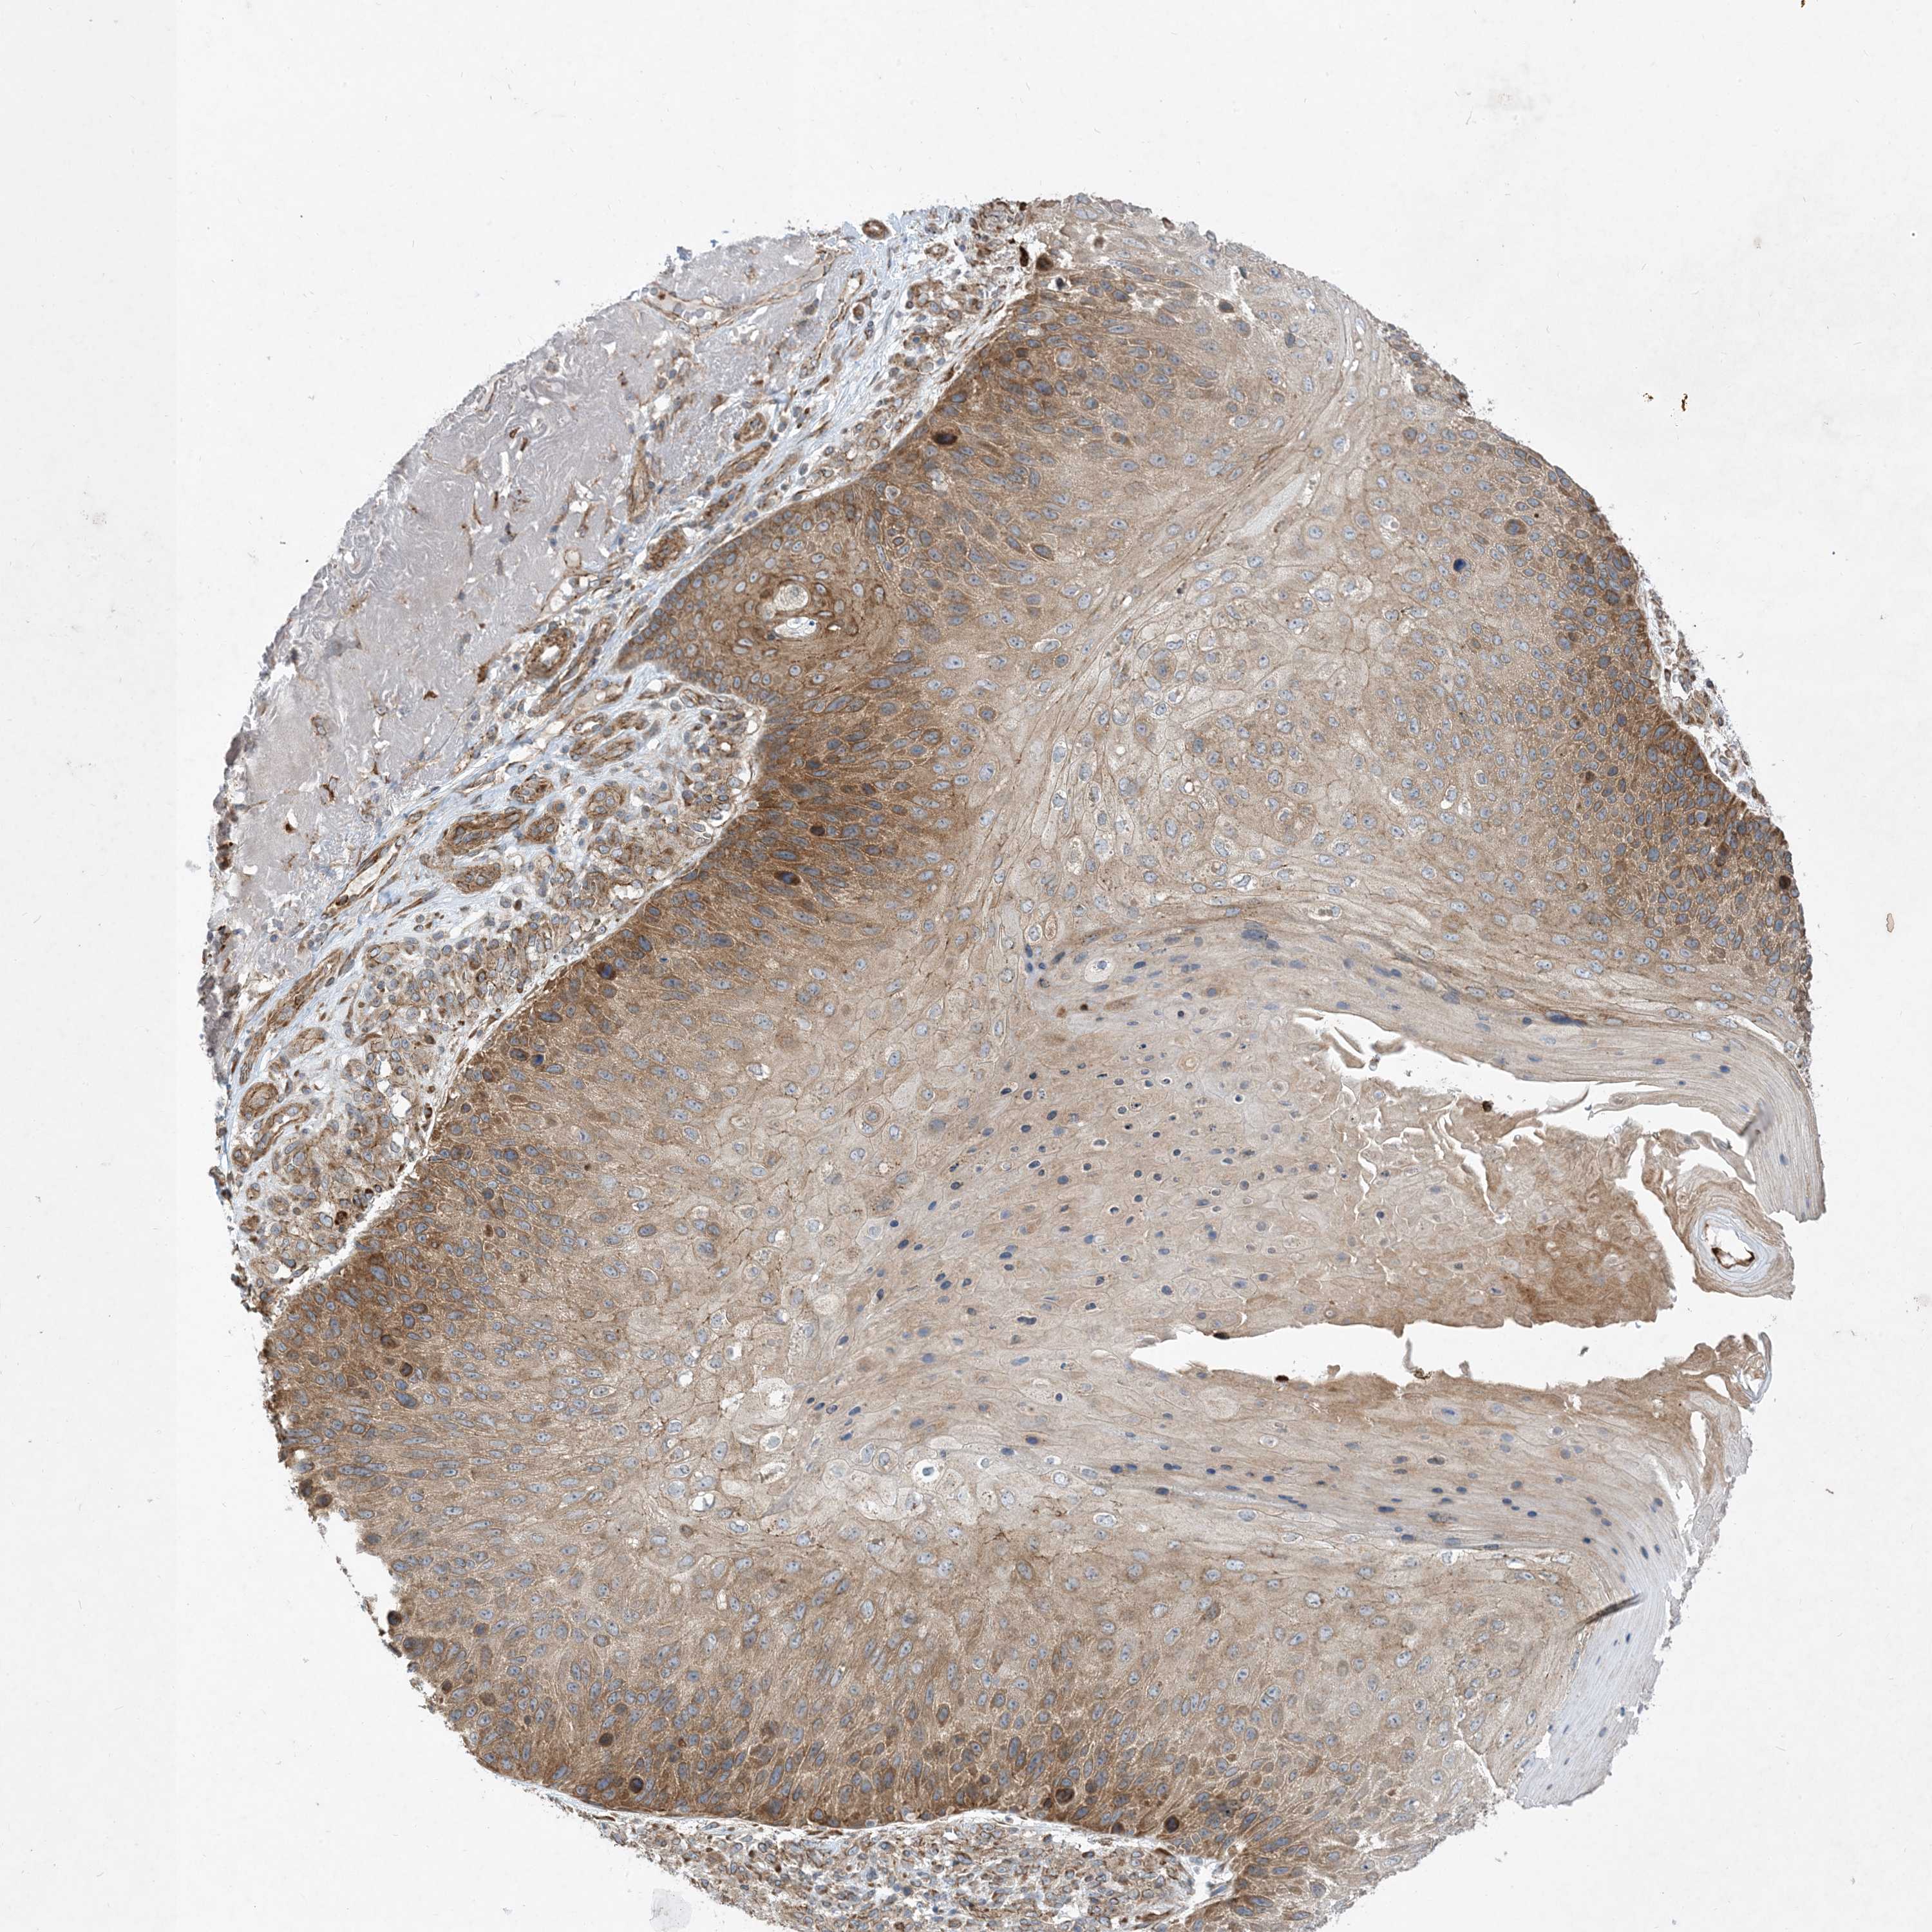

Basal cell and squamous cell cancer

SKIN CANCER - Protein expressioni

A mouse-over function shows sample information and annotation data. Click on an image to view it in a full screen mode. Samples can be filtered based on level of antibody staining by selecting one or several of the following categories: high, medium, low and not detected. The assay and annotation is described here.

Antibody stainingi

Antibody staining in the annotated cell types in the current human tissue is reported as not detected, low, medium, or high, based on conventional immunohistochemistry profiling in selected tissues. This score is based on the combination of the staining intensity and fraction of stained cells.

Each image is clickable and will lead to virtual microscopy that enables deeper exploration of all samples and also displays staining intensity scores, fraction scores and subcellular localization as well as patient and tissue information for each sample.

Antibody HPA035599

Staining

High

Intensity

Strong

Quantity

>75%

Location

Nuclear

Basal cell carcinoma